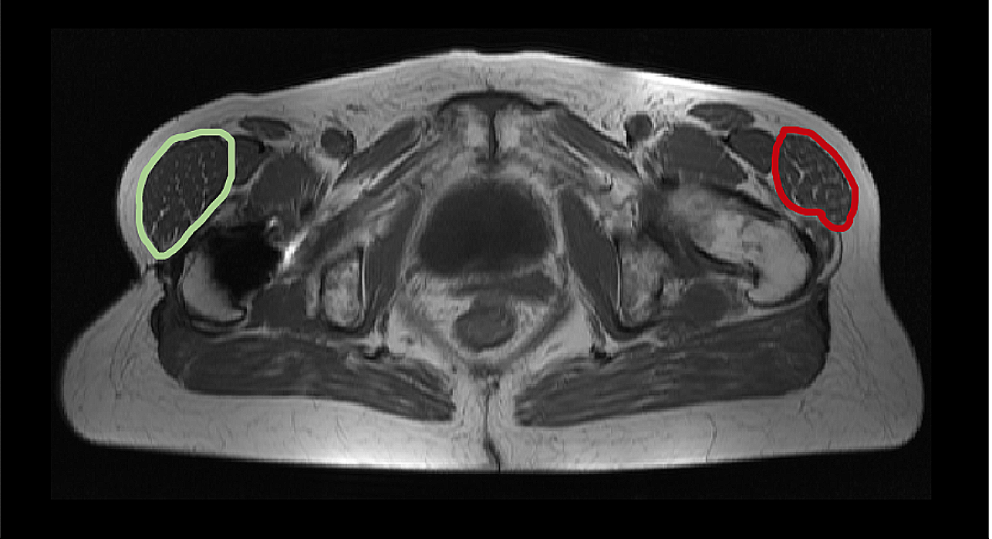

The present study shows satisfying results regarding the postoperative muscle volume. Despite the invasiveness of the procedure, overall no significant further loss of total muscle volume was seen. Due to the progressive nature of muscular degeneration, these findings can be interpreted as treatment success. The detailed results present some remarkable changes in muscle tissue that have to be discussed. A trend toward a compensatory growth of the TFL volume can be seen postoperatively. The Gmed as the strongest abductor with the highest level of degeneration preoperatively demonstrated no significant further loss of total volume during the follow-up period. The moderate total volume loss of Gmax is explainable due to the invasive operative procedure. The measurements of the present study indicate that no further loss of the Gmax muscle volume can be verified, despite the part used and elevated as a flap. The lean muscle volume exhibited better postoperative results for all measured muscles, indicating a postoperative growth of functional muscle tissue of the abductor mechanism. In particular, the significant growth of the Gmin and the TFL has to be pointed out. It can be assumed that abduction-supportive muscles such as the TFL grow as a compensation (Fig. 3). A study of Damm et al. with a short-term follow-up of three months after THA also reported a significant increase in TFL lean volume and a decreased Gmin volume postoperatively [28]. A decreased Gmin volume contrasts the findings of the present study and can be explained by the largely different follow-up period. However, the TFL seems to play an important role to compensate for the loss of the gluteal muscles during THA.

Fig. 3

Example of postoperative measurements compared to the unaffected side. Postoperative MRI of the pelvis (T1, transversal plane) of a 56-year-old patient with a chronic gluteal deficiency of the right abductor mechanism after total hip arthroplasty treated with a gluteus maximus transfer. The MRI images 11 months after surgery presenting a compensatory growth of the right musculus tensor facia lata (green) compared to the opposite and unaffected left side (red)